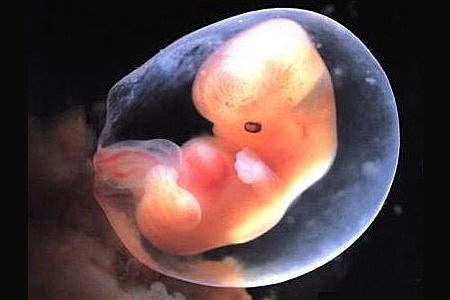

• Semana 3

3

Semana 3

En el disco embrionario se crea una estructura, la notocorda (condiciona la migración de células para que formen una tercera capa llamada mesodermo).

El mesodermo al final de la semana, ocurren a los lados del tubo neuralunos pares llamados somitas, donde las células emigran para empezar a formar: tejido conectivo, la capa profunda de la piel, miotomos (forman músculos), cartílago, hueso, tejido adiposo, hematopoyético, epitelio, uréteres,peritoneo, pericardio,gónadas, etc.

• Semana 4

4

Semana 4

A los 24 días se aprecian los dos primeros arcos faríngeos:

-1er. Arco : ARCO MANDIBULAR.

-2do. Arco : ARCO HIOIDEO.

-El prosencéfalo crea una elevación prominente de la cabeza y el pliegue embrionario otorga al embrión una curva en forma de C.

-Los esbozos de los miembros superiores se reconocen hacia el día 26 y 27 como pequeñas tumefacciones en las paredes corporales ventrolaterales.

-El embión se introduce en la pared uterina y comienza a nutrirse través de esta.